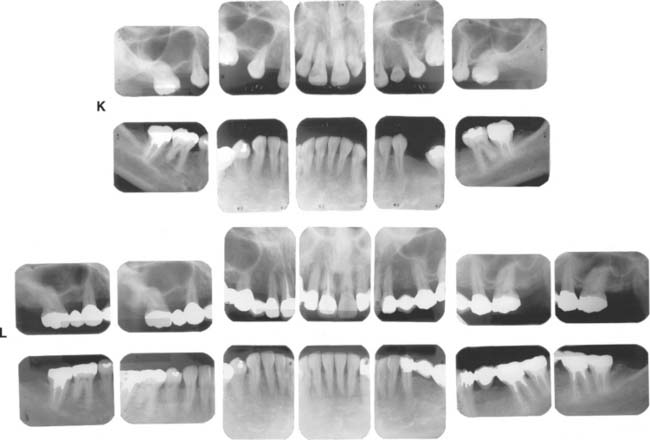

Detecting disease around an FDP can be extremely difficult at a stage when corrective treatment is still relatively simple. For instance, partial dissolution of the luting agent may be difficult to diagnose with a subgingival margin. Caries is often detected only after irreversible pulp involvement has resulted. Caries under a crown is more difficult to detect radiographically, although bitewing images provide some information interproximally. Follow-up studies on patients with FDPs reveal that identifying risk factors and predicting the development of caries in any particular patient are complicated. However, there is no indication that caries is more likely in association with prostheses than on unrestored teeth.3

If caries is overlooked, disease may rapidly progress to the point at which the fabrication of a new prosthesis becomes inevitable or, even worse, tooth loss results.

Dental caries (Fig. 32-8) is the most common cause of failure of a cast restoration.9-12 Detection can be very difficult,13 particularly where complete coverage is used. At each appointment, the teeth should be thoroughly dried and visually inspected (Fig. 32-9). The explorer must be used very carefully when early enamel lesions are assessed, because a heavy-handed examination may damage the fragile demineralized enamel matrix. An intact enamel matrix is essential for procedures that induce remineralization14 (e.g., improved plaque control, dietary changes, topical fluoride applications).

Fig. 32-8 Undetected caries beneath this partial fixed dental prosthesis resulted in serious complications.